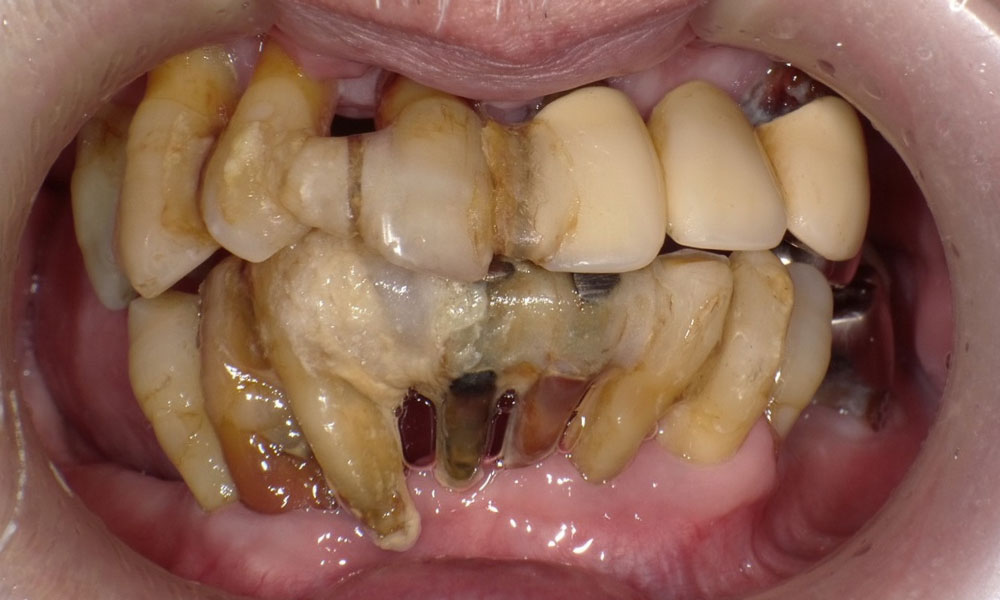

手術前口腔内

全体的に歯がボロボロで噛むと痛みがあると訴えあり。インプラント埋入可能な歯槽骨量が少なく、残存歯も抜歯対象のため上下ザイゴマインプラント治療を選択。